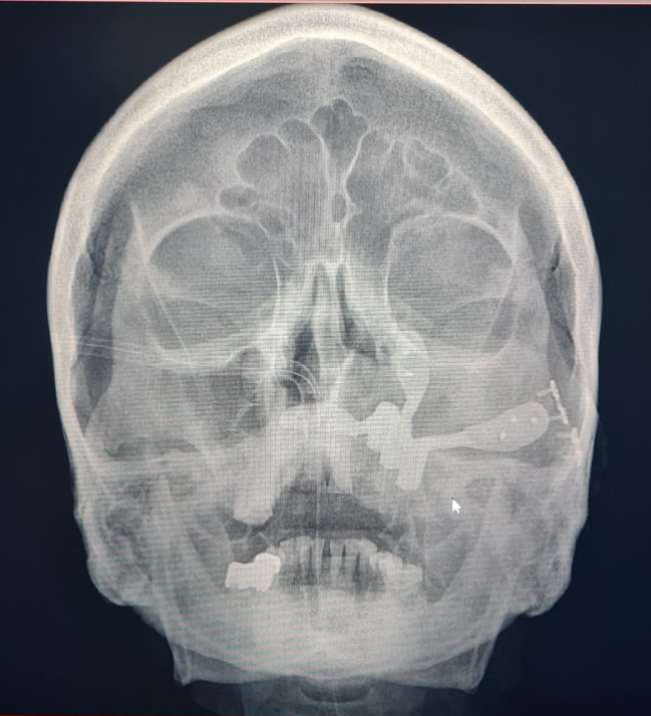

Figure 7: Post op PA view

Figure 7